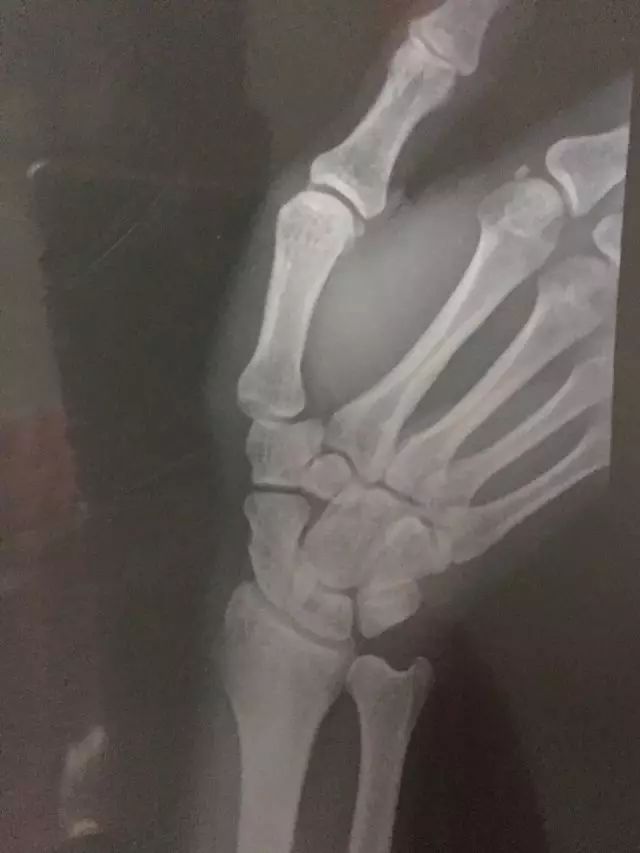

您好,蔡队,我是羽毛球爱好者,在训练过程中受伤导致三角骨韧带撕裂,想麻烦您帮忙看看如何恢复,已经2个月了,还是有疼痛感

----韧带伤主要还是固定,给韧带修复的时间。建议减少活动,否则可能迁延不愈。